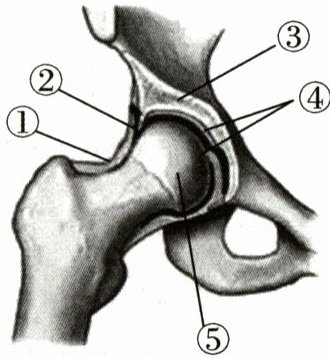

6. 冰壶运动中,髋关节的灵活性能让运动员在投壶时维持较低的身体重心,增加投壶的稳定性。如图是髋关节结构示意图,下列叙述不正确的是(

A.关节由①②③构成

B.结构②中有滑液

C.结构④使关节灵活

D.⑤从③中滑脱出来导致关节脱位

A

)A.关节由①②③构成

答案:

6.A